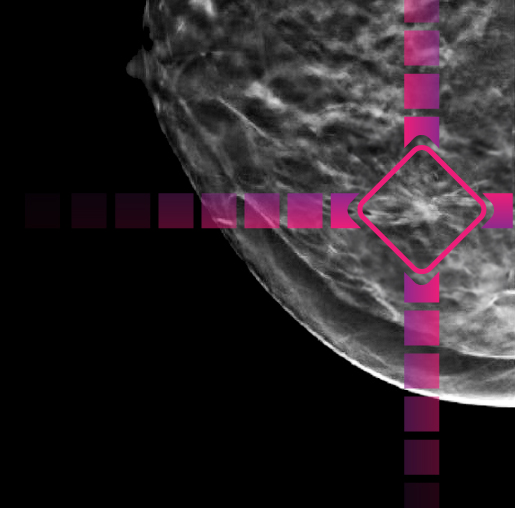

After your exam, Artificial Intelligence (AI) technology1 is applied to your mammogram.

The AI points out areas of interest on your exam to help the radiologist detect very subtle abnormalities.

After your radiologist reads your exam, the AI performs a second review.

1. Saige-DX™ Artificial Intelligence, powered by DeepHealth.